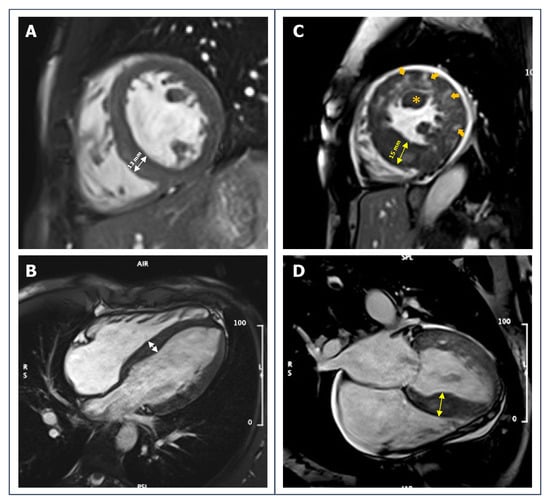

- Caselli, S.; Maron, M.S.; Urbano-Moral, J.A.; Pandian, N.G.; Maron, B.J.; Pelliccia, A. Differentiating left ventricular hypertrophy in athletes from that in patients with hypertrophic cardiomyopathy. Am. J. Cardiol. 2014, 114, 1383–1389. [Google Scholar] [CrossRef] [PubMed]

- Maron, M.S.; Lesser, J.R.; Maron, B.J. Management implications of massive left ventricular hypertrophy in hypertrophic cardiomyopathy significantly underestimated by echocardiography but identified by cardiovascular magnetic resonance. Am. J. Cardiol. 2010, 105, 1842–1843. [Google Scholar] [CrossRef]

- Moon, J.C.C.; Fisher, N.G.; McKenna, W.J.; Pennell, D.J. Detection of apical hypertrophic cardiomyopathy by cardiovascular magnetic resonance in patients with non-diagnostic echocardiography. Heart 2004, 90, 645–649. [Google Scholar] [CrossRef]

- Rickers, C.; Wilke, N.M.; Jerosch-Herold, M.; Casey, S.A.; Panse, P.; Panse, N.; Weil, J.; Zenovich, A.G.; Maron, B.J. Utility of cardiac magnetic resonance imaging in the diagnosis of hypertrophic cardiomyopathy. Circulation 2005, 112, 855–861. [Google Scholar] [CrossRef]

- Petersen, S.; Selvanayagam, J.; Francis, J.; Myerson, S.; Wiesmann, F.; Robson, M.; Östman-Smith, I.; Casadei, B.; Watkins, H.; Neubauer, S. Differentiation of athlete’s heart from pathological forms of cardiac hypertrophy by means of geometric indices derived from cardiovascular magnetic resonance. J. Cardiovasc. Magn. Reson. 2005, 7, 551–558. [Google Scholar] [CrossRef]

- Czimbalmos, C.; Csecs, I.; Toth, A.; Kiss, O.; Suhai, F.I.; Sydo, N.; Dohy, Z.; Apor, A.; Merkely, B.; Vago, H. The demanding grey zone: Sport indices by cardiac magnetic resonance imaging differentiate hypertrophic cardiomyopathy from athlete’s heart. PLoS ONE 2019, 14, e0211624. [Google Scholar] [CrossRef]